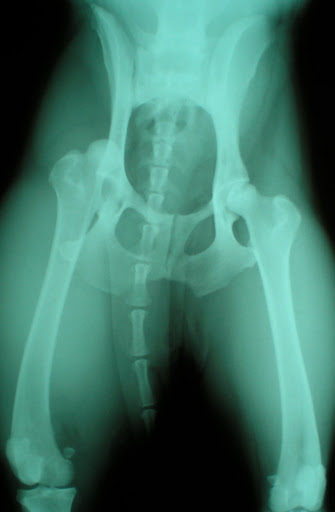

Σκύλος προσκομίστηκε στο Κτηνιατρικό Κέντρο Ιλισίων μετά από τροχαίο ατύχημα. Διαπιστώθηκαν εξάρθρημα ισχίου, κάταγμα ηβοισχιακής σύμφυσης, εξάρθρημα μεταξύ έκτου καί έβδομου οσφυϊκών σπονδύλων καί κατάγματα ακανθώδους απόφυσης καί κάτω οπίσθιας γωνίας σώματος έκτου οσφυϊκού σπονδύλου. Λίγες ημέρες μετά το ατύχημα εμφανίστηκαν αταξία καί απώλεια των αντανακλαστικών θέσης των οπισθίων άκρων καθώς και αδυναμία κίνησης της ουράς. Παρακάτω φαίνονται οι ακτινογραφίες του εξαρθρωμένου ισχίου πρίν και μετά την κλειστή ανάταξη, οι ακτινογραφίες της σπονδυλικής στήλης πρίν και μετά τη χειρουργική επέμβαση (τροποποιημένη τμηματική νωτιαία σταθεροποίηση) και τα εμφυτεύματα αμέσως μετά την ολοκλήρωση της τοποθέτησής τους και λίγο πριν την έναρξη συρραφής του χειρουργικού τραύματος.